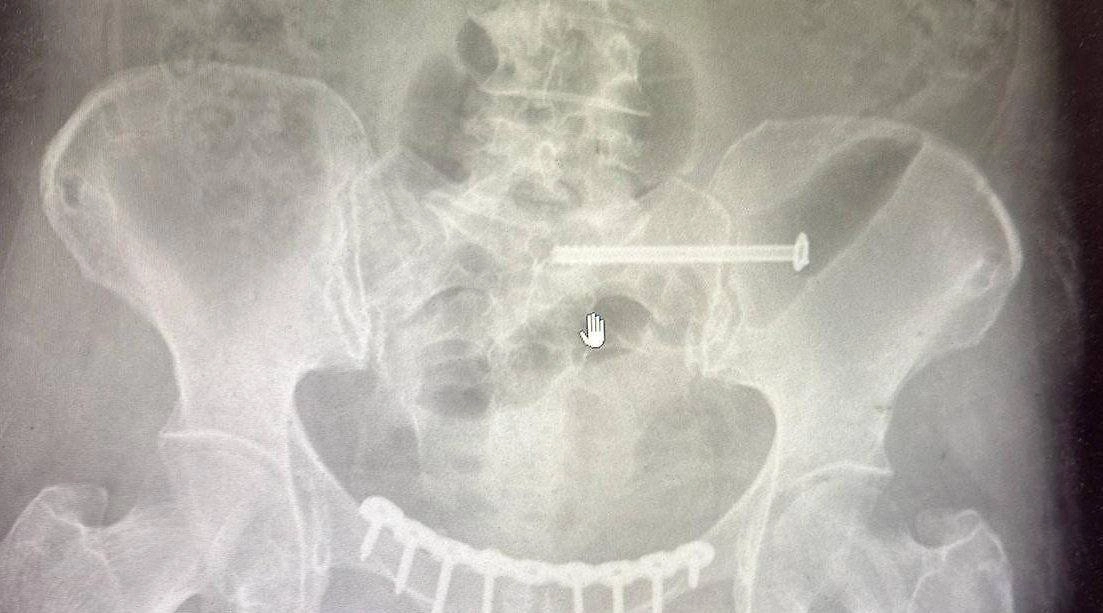

Врачи обнаружили сочетанное повреждение — разрыв лонного и крестцово-подвздошного сочленений, из-за которых тело теряет стабильность и способность выдерживать нагрузку. Медики сразу приняли решение оперировать.

«Мы выполнили остеосинтез — соединили обломки костей специальными пластинами и винтами. Это титан, он безопасен и его не нужно удалять», — объяснил травматолог-ортопед Салман Асламханов.